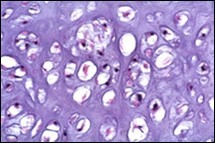

Figure 4.Enchondroma depicting lobules of hyaline cartilage with vacuolated cells and eccentric nuclei 12.

Figure 5.Enchondroma enunciating lobules of uniform cartilaginous cells with regular, centric nuclei and absence of mitosis 13.